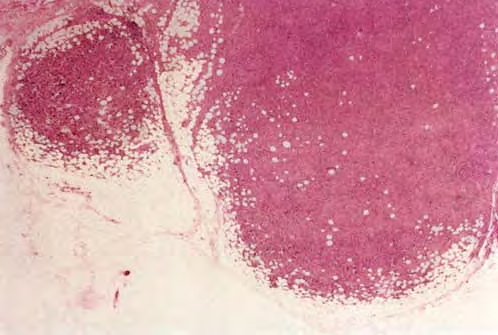

malignant-lymphoma-b-Cell-type